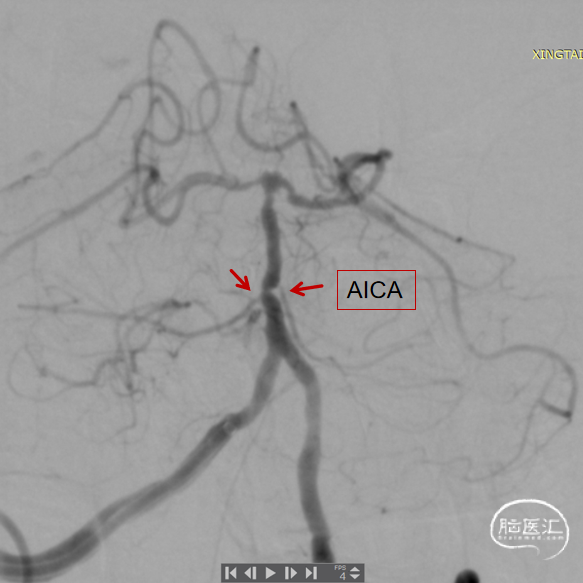

基底动脉狭窄位于双侧AICA开口处,且无双侧PICA,其供血区由双侧AICA、SCA分支代偿供血。

术中如何扩张基底动脉的同时保护双侧AICA通畅是手术成功的关键。

术后造影:基底动脉狭窄消失,双侧AICA通畅。